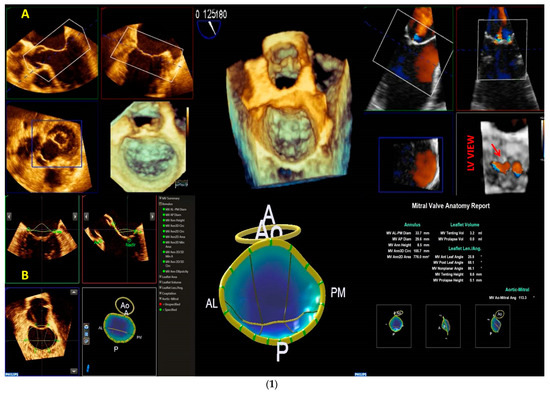

2.2. Mitral Valve Quantification (MVQ) and Mitral Valve Navigation (MVN)

3.2. Quantification of the Morphology